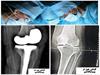

![]() انجام عمل جراحی تعویض مفصل در بیمارستان جوین رئیس بیمارستان قمربنی هاشم(ع)گفت:عمل جراحی پروتزگذاری (توتال آرتوروپلاستی)دیگری در بیمارستان جوین با موفقیت رقم خورد. | |